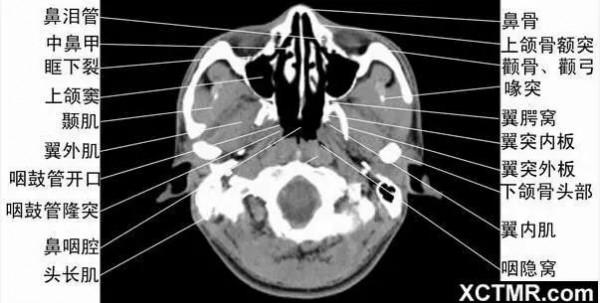

頭頸五官CT斷層解剖圖及常見病影像診斷

頭頸五官CT斷層解剖圖